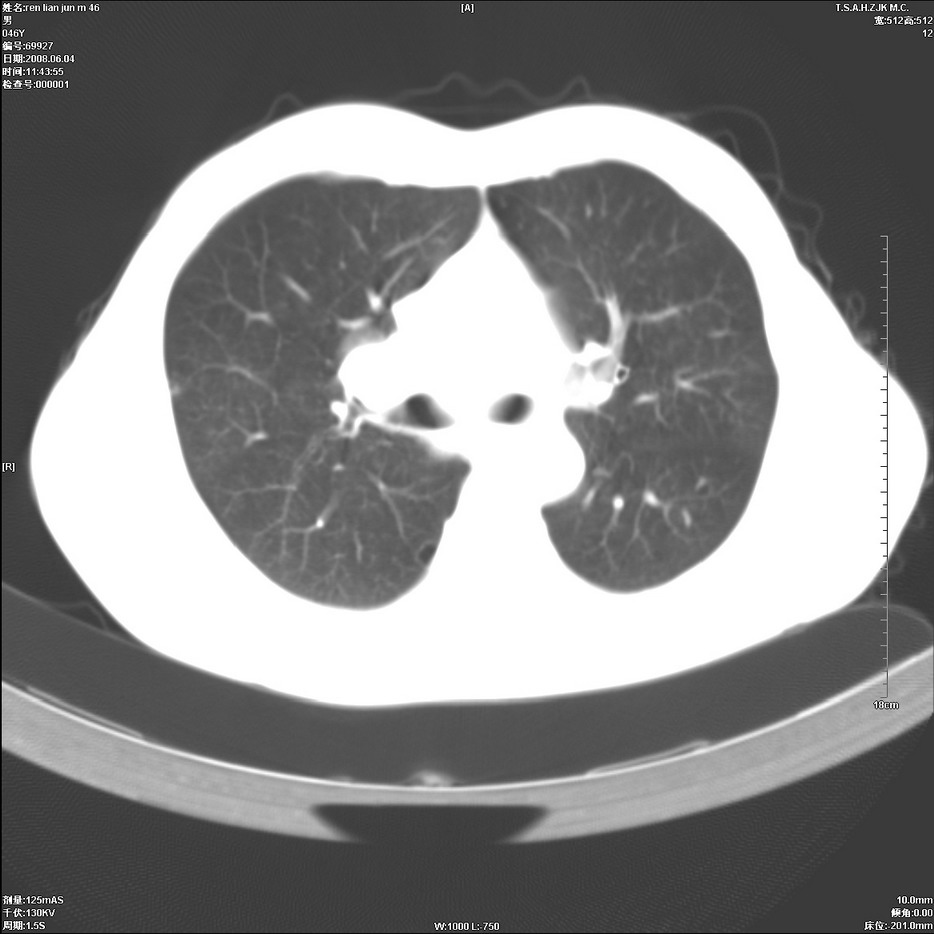

以下是引用qiu999在2008-6-5 17:14:00的发言:[br]考虑右肺中心型肺癌.颅内应做增强检查.

以下是引用形影不离在2008-6-5 19:18:00的发言:[br]右肺中心型肺癌并纵隔及左侧腋窝淋巴结转移,颅内应做增强检查。

以下是引用杀毒软件在2008-6-5 18:33:00的发言:[br]支持考虑右肺中心型肺癌,颅内病变是不是转移,不好说